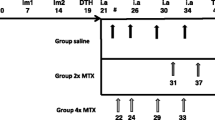

Further development of folate imaging agents also focused on PET tracers, which could be used for detection of (sub)clinical arthritis as well as for more accurate therapy monitoring. To this end, a folate PET tracer, [18F]-fluoro-PEG-folate, was synthesized in a two-step procedure and evaluated in an antigen-induced arthritis model in rats [48]. Uptake of [18F]-fluoro-PEG-folate was significantly higher in arthritic than in non-inflamed control knees, and also arthritic knee to bone and arthritic knee to blood ratios were higher for [18F]-fluoro-PEG-folate than (R)-[11C]PK11195 [48]. In addition, using [18F]-fluoro-PEG-folate PET, it was possible to monitor therapeutic effects of MTX in arthritic rats [49] and to monitor systemic inflammatory effects in an arthritic rat model [50]. Based on these encouraging preclinical results, [18F]-fluoro-PEG-folate was taken to a clinical setting in which this tracer could readily visualize arthritic joints in RA patients [130]. Recently, a novel folate-based PET tracer was synthesized in a faster (< 1 h) one-step procedure, i.e., [18F]-folate-PEG-NOTA-Al [131], which warrants further (pre)clinical evaluation.